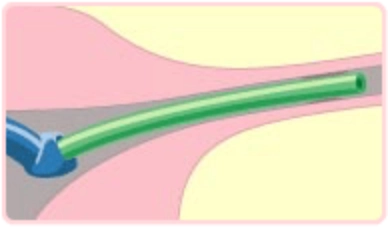

細い内視鏡(卵管鏡)を内蔵した細い管(カテーテル)を用意します。

カテーテルを腟から子宮へと挿入し、卵管に近づけます。

カテーテルの風船(バルーン)を膨らませて、卵管の中へバルーンを進めます。

卵管内の全域で詰まっているところを広げます。

卵管内の様子を、卵管鏡を使って観察します。

※提供:テルモ株式会社